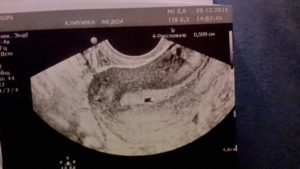

Очень волнительный момент – наступление ожидаемой беременности. Три дня задержки, две полоски на тесте, купленном в ближайшем супермаркете, и женщина уже уверена, что желанное зачатие осуществилось. Однако для точного подтверждения этого факта, а также чтобы убедиться, что плодное яйцо, из которого вырастет будущий малыш, находится именно там, где должно, необходимо сделать УЗИ матки.

Женщина обращается к своему гинекологу, тот назначает ультразвуковую диагностику, но по итогам в заключении указано, что результат отрицательный: на УЗИ раннюю беременность не видно. Иногда бывает так, что и через месяц или чуть больше после положительного теста, УЗИ беременность не покажет. Почему так случается?

Когда делать УЗИ после положительного теста?

Чтобы быть уверенной в правдивости исследования, женщине нужно понимать, с какого срока на УЗИ видно беременность. Тест, как правило, проводится в первые дни задержки менструального цикла.

Этот срок соответствует приблизительно от двух до четырех недель беременности. Поэтому не стоит бежать на УЗИ сразу после проведенного теста, 2 недели – слишком рано для качественной диагностики.

А более-менее достоверными результаты УЗИ будут к концу второго месяца, то есть к 8 неделе.

В первые недели развития эмбриона имеет смысл выполнять только трансвагинальное УЗИ.

Это обследование предполагает, что датчик вытянутой формы небольшого диаметра вводят во влагалище женщины и получают с его помощью изображение матки на мониторе аппарата.

В связи с тем, что датчик максимально приближен к изучаемой зоне, тонность исследования очень высокая. Специфической подготовки такое УЗИ не требует. Оно безопасно и не приносит осложнений.